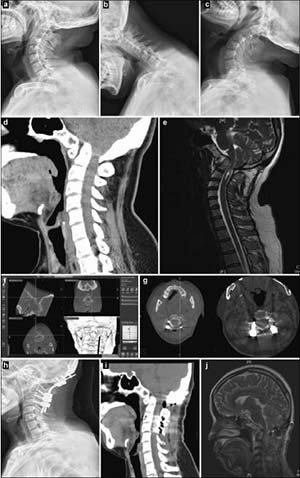

20171023161042 Figure 1 Preoperative, intraoperative, and postoperative images of patients with atlantoaxial dislocation and occipitocervical fusion. Preoperative cervical radiography in the side (a), anteflexion (b), and supine (c) positions reveals odontoid instability and a backward and upward shift. Preoperative computed tomography (CT) (d) and magnetic resonance imaging (MRI) (e) show that the backward and upward dislocation of the C2 odontoid impacts the brain stem. The foramen magnum is narrow, and the cervical cord void is visible. (f) Implantation direction and C2 angle. Pars screws are planed under intraoperative navigation. (g) O-arm three-dimensional scan, after screw implantation, shows that the Pars screw to the right of C2 penetrates the bone cortex and is near the vertebral artery. Lateral radiography (h), sagittal CT (i), and a T2 sagittal scan (j), 1 week after the operation, show firm screw fixation in a good position and inferoanterior displacement of the odontoid to the C1 level, essentially achieving normal anatomical reduction. Brain stem compression is released, and the posterior cranial fossa is fully decompressed.